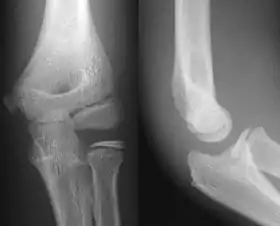

AP and lateral elbow X-ray

• Elbow - AP and Lateral. Radial head projections available on request

• Knee - AP and Lateral. Intra Condular projections on request

• Soft tissues are seen with the same machine as for hard tissues, but a "softer" or less-penetrating X-ray beam is used. Tissues commonly imaged include the lungs and heart shadow in a chest X-ray, the air pattern of the bowel in abdominal X-rays, the soft tissues of the neck, the orbits by a skull X-ray before an MRI to check for radiopaque foreign bodies (especially metal), and of course the soft tissue shadows in X-rays of bony injuries are looked at by the radiologist for signs of hidden trauma (for example, the famous "fat pad" sign on a fractured elbow).